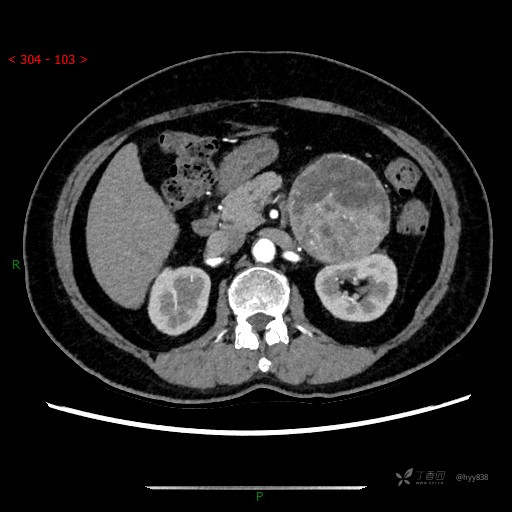

中腹部CT平扫